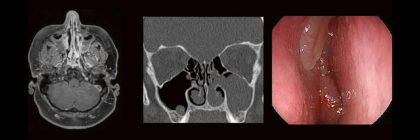

Professor Dr. med. Marc Brockmann WEITERENTWICKLUNGEN VON KOPF BIS FUSS BEIM VC Oberstarzt Dr. med. Stephan Waldeck DEEP-LEARNING-REKONSTRUKTION IN DER NEURORADIOLOGIE Die CT ist ein essentielles Routine-Verfahren in der Neuroradiologie. Weiterlesen …